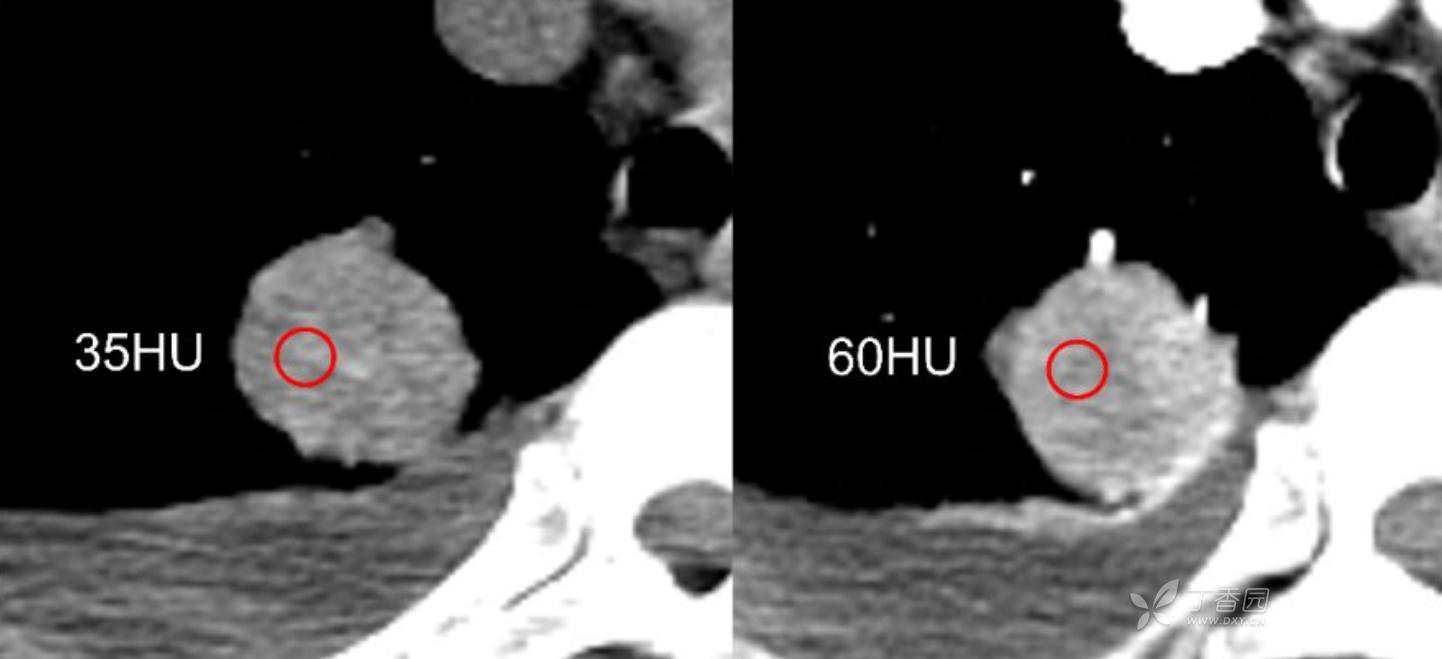

简要病史:乏力、纳差20余天,皮肤巩膜黄染半月偶有咳嗽,咳白痰,全身皮肤巩膜黄染。无咯血,无明显胸闷、胸痛,无明显气促,无发热及盗汗。精神欠佳,纳差,睡眠一般,二便正常